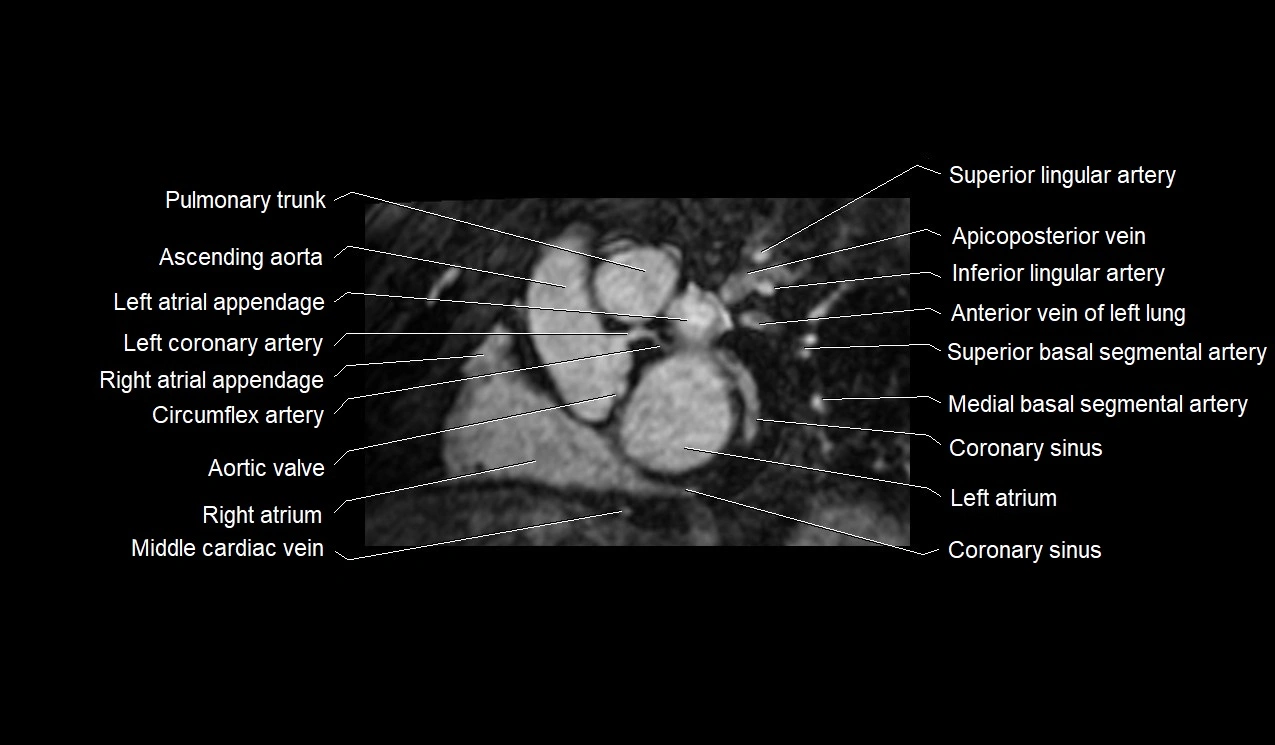

MRI image